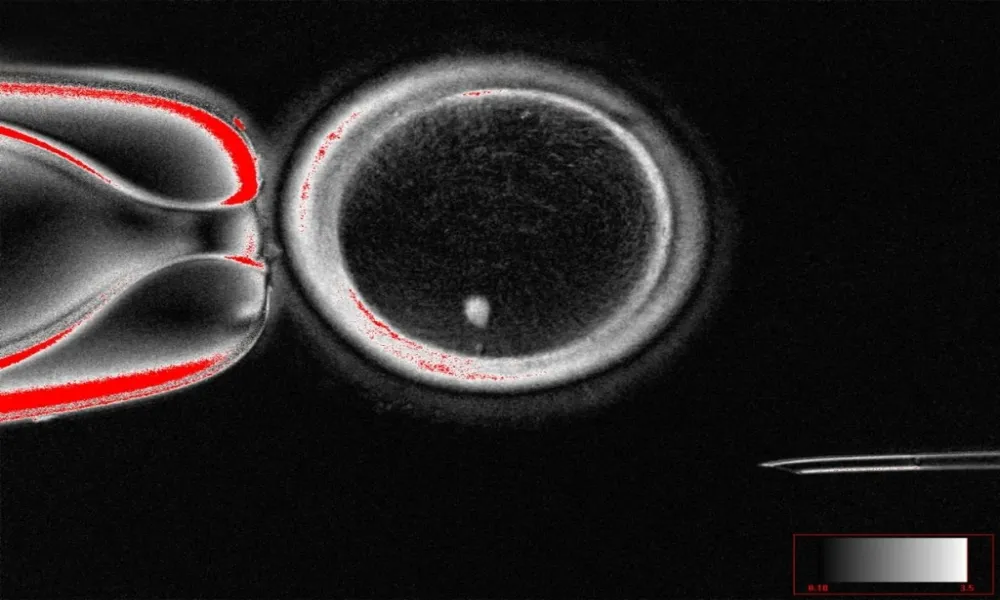

Header Image